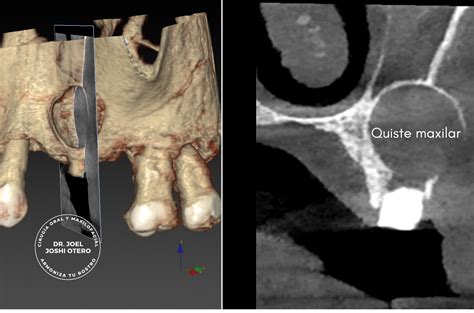

En odontología, la detección temprana de afecciones como los quistes maxilares es crucial, ya que pueden pasar desapercibidas durante meses si no se identifican en una revisión rutinaria. Un quiste maxilar se define como una cavidad anómala dentro del hueso maxilar, superior o inferior, que se caracteriza por estar recubierta por una membrana epitelial y que puede contener líquido, aire o material semisólido.

El queratoquiste odontogénico es una tumoración quística cuya cápsula está formada por epitelio escamoso derivado de la lámina dental o el epitelio odontogénico primordial. Representa aproximadamente el 10% de todas las lesiones quísticas que se manifiestan en los maxilares.

Es localmente agresivo, recidiva con frecuencia y, ocasionalmente, se asocia con displasia epitelial o incluso carcinoma epidermoide. Radiológicamente, es raro que presentes reabsorciones radiculares. El diagnóstico está basado en las características histológicas.